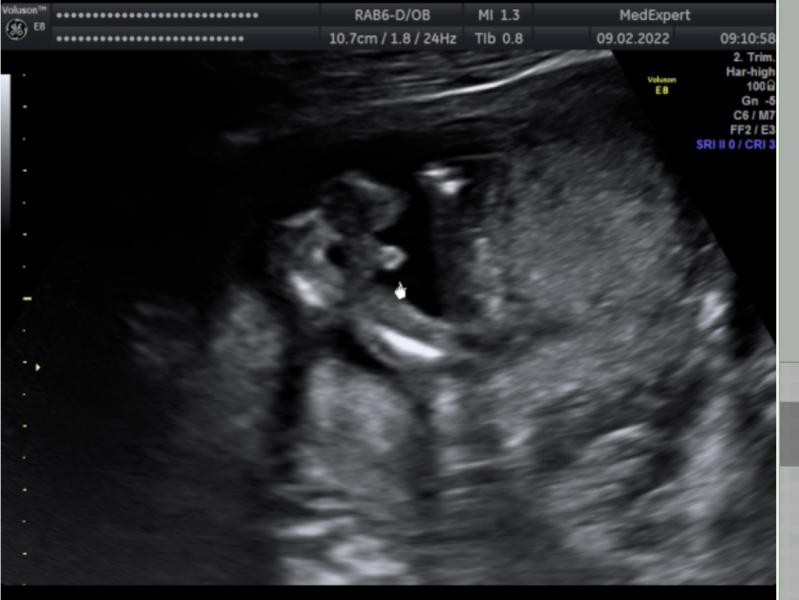

Почему-то все время была уверена , что будет девочка. Плюс высокий хгч в начале беременности, везде все пишут что такой у девочек ( 9дпп - 211; 11 дпп - 630; 14 дпп - 2630). Потом ЧСС 178 на 1 скрининге , тоже здесь видела , что такое высокое у девочек ))) и была вчера просто в шоке, когда увидела это 🙈и врач сказала 100% мальчик . Но я счастлива , все равно кто, так как 3,5 года мы тебя ждали малыш ❤️

Ооо, все как у меня. И чсс 178. И тоже сказали мальчик, и фото такое же. Только я ещё сомневалась, не ошиблись ли🤣